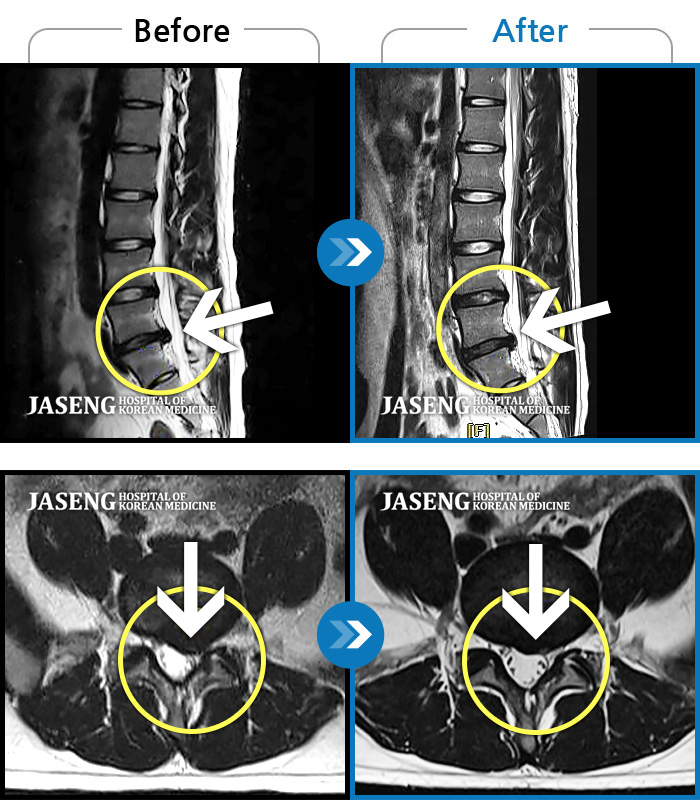

Before

After

허리 양측 둔부에서 발가락으로 통증, 비증, 힘이 빠지는 증상

2018.08.11 ~ 2019.03.27